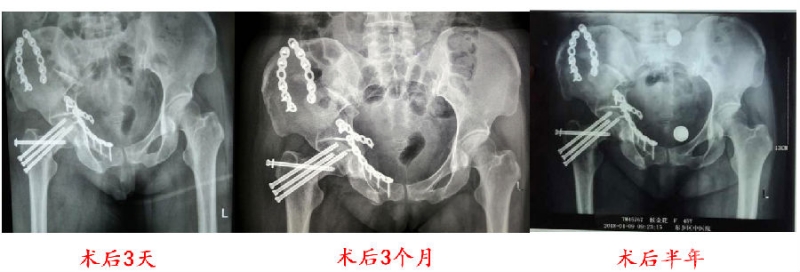

手术过程:

(1)取出原空心螺钉;

(2)DAA入路;

(3)关节囊内沿原骨折线截骨外展;

(4)将侧位后仰的股骨头恢复前倾;

(5)克氏针临时固定,术中透视位置可,颈干角恢复;

(6)髂骨自体取骨,楔形骨块植于股骨颈内侧支撑;

(7)空心螺钉+钢板内固定。

影像学资料

术后3个月回医院随访(8月初):

(1)局部压痛及纵轴叩击痛消失;

(2)复查X线内固定物位置良好,骨折线已经模糊。